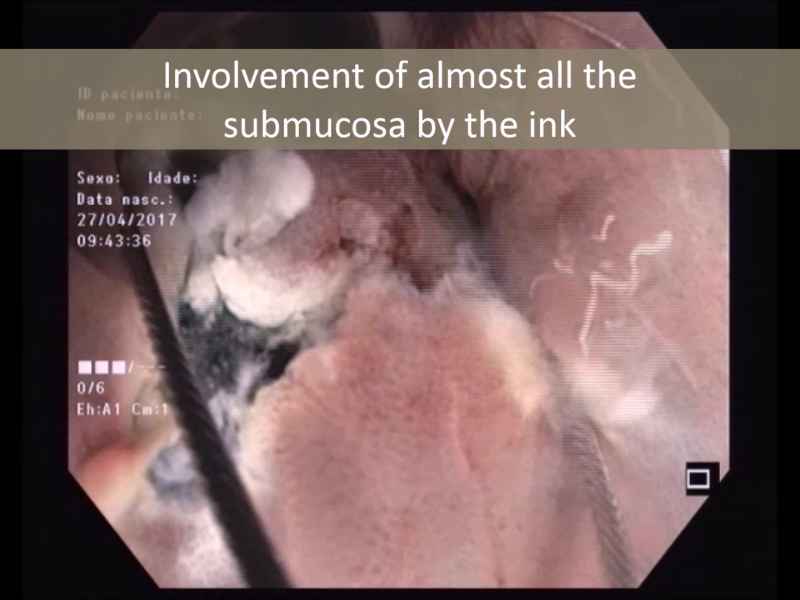

Underwater Endoscopic Mucosal Resection of a Lateral Spreading Tumor Overlying an Endoscopic Carbon Tattoo

Vídeo